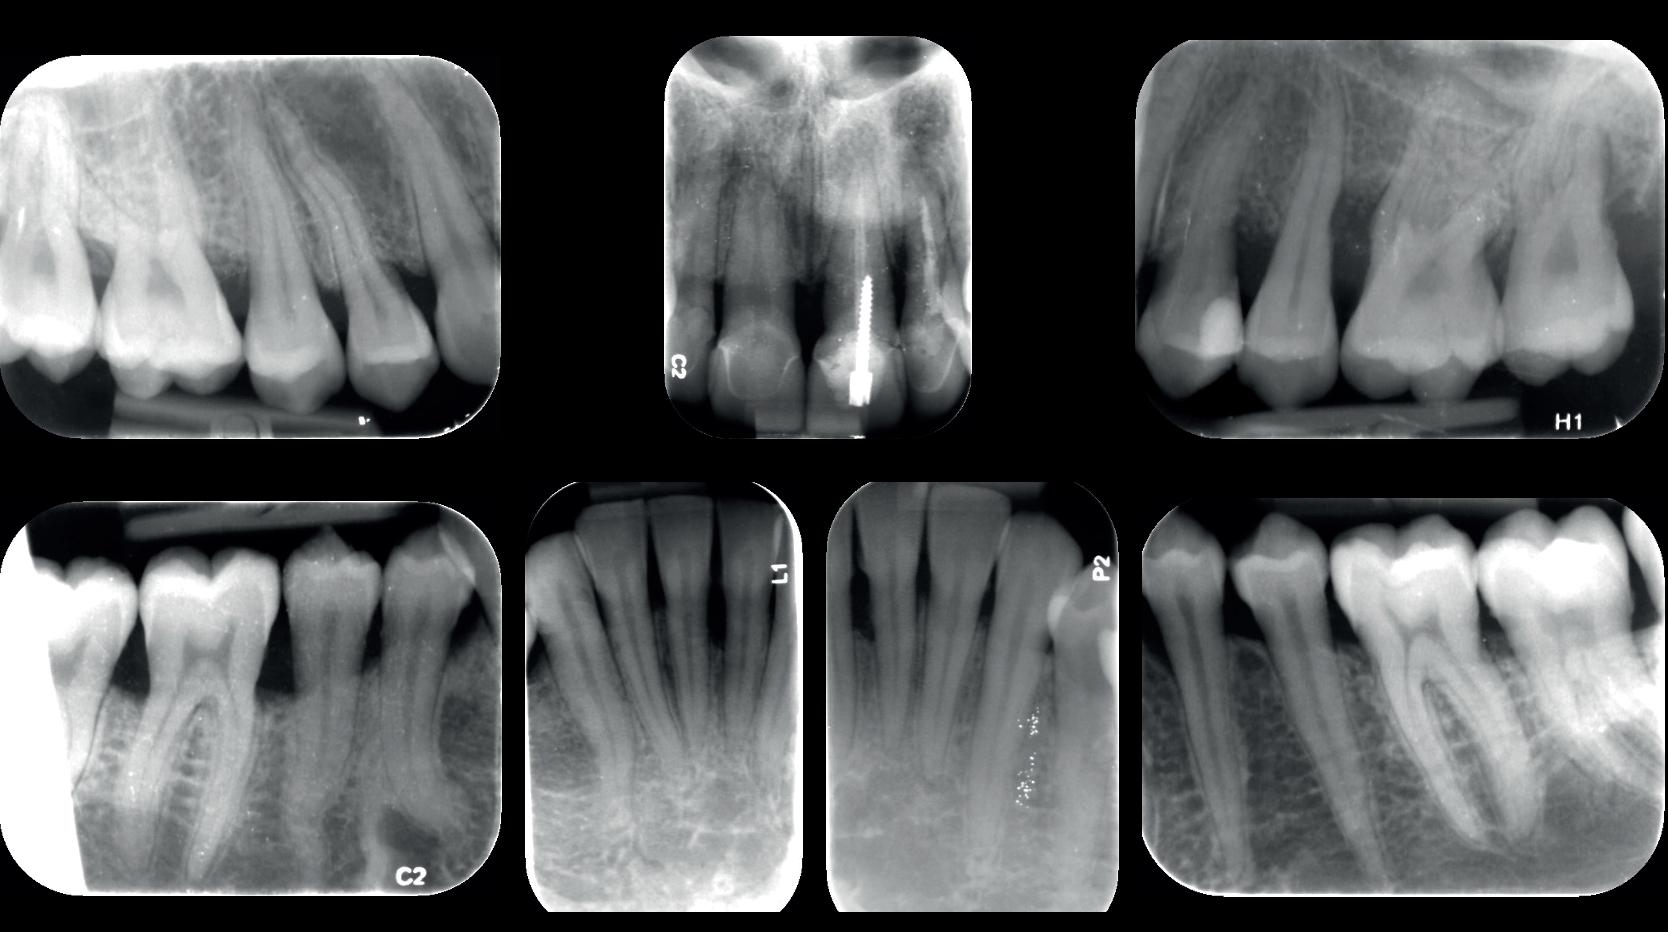

De diagnose luidde lokaal parodontitis met ernstige furcatie aandoeningen; Stadium IV (vergevorderd); graad C (snel progressief) (afbeelding 7) De elementen die niet te behouden waren, werden geëxtraheerd.

Na afronding van de eerste twee behandelstappen werd parodontale stabiliteit bereikt, zoals waarneembaar op de parodontiumstatus en (röntgen)foto’s (afbeelding 6, 8). De patiënt toonde aantoonbare verbetering in mondhygiëne (afbeelding 4) en bleef gemotiveerd om de behandeling voort te zetten.

5. OPT intake

6. OPT na infectie controle

7. Parodontium status intake

8. Parodontiumstatus na infectie

controle

10. OPT-implantaten

9). In de bovenkaak werd bilateraal een sinuslift uitgevoerd. Aansluitend werden in beide kaakhelften implantaten geplaatst (afbeelding 10).